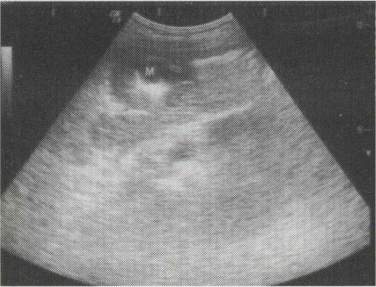

50.女,26岁,停经23周。产前B超检查如图,结合超声图像,最可能的诊断为()